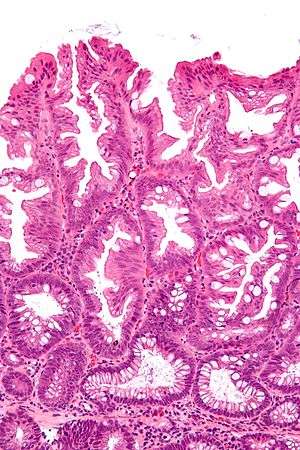

Intermediate magnification micrograph of a SSA.

SSAs are diagnosed by their microscopic appearance; histomorphologically, they are characterized by (1) basal dilation of the crypts, (2) basal crypt serration, (3) crypts that run horizontal to the basement membrane (horizontal crypts), and (4) crypt branching. The most common of these features is basal dilation of the crypts.

Unlike traditional colonic adenomas (e.g. tubular adenoma, villous adenoma), they do not (typically) have nuclear changes (nuclear hyperchromatism, nuclear crowding, elliptical/cigar-shaped nuclei).